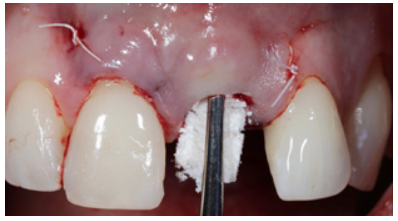

Subsequently, to guarantee the stability of the soft tissues and to anticipate the remodelling of the hard tissue resulting in vestibular defects, bone preservation of the vestibular region of the alveolus was carried out. A collagen-reinforced bone xenograft (Bio-Oss™ Collagen, Geistlich) was used, which was placed in the gap between the vestibular cortical bone and the implant itself (Figure 15).

To complete the surgical approach, the provisional prosthesis was placed with the already made PE and 3 points of coronal traction were carried out, anchoring them to the contact points of the provisional and adjacent teeth with a 6.0 monofilament suture (Figure 16).